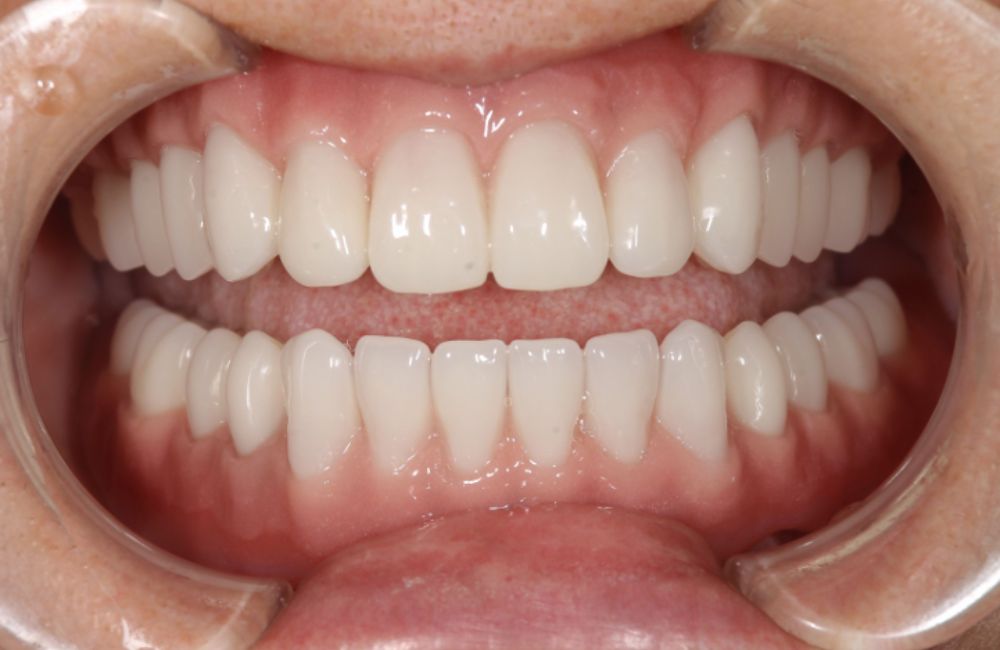

治療前と治療後の口腔内写真と顔貌変化

インプラントオーバーデンチャーの装着前と装着後